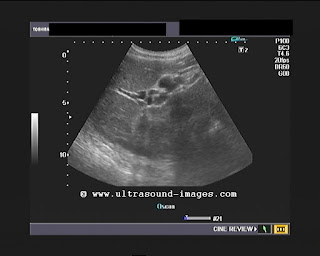

Portal cavernoma Vs portal biliopathy- a sonographic case study

This elderly male patient had generalized discomfort in the abdomen with vague pain in the epigastrium. No h/o alcoholism.